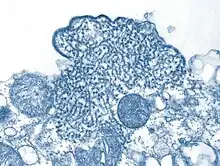

| Structure of a Henipavirus | |